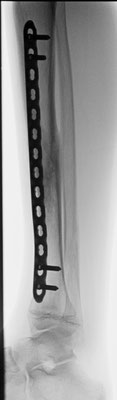

Stark verschobener Unterschenkelbruch bei einem 14- jährigen. Minimal-invasive Stabilisierung mit winkelstabiler Platte. Das Bein kann nach Abklingen der akuten Schwellung bereits wieder mit 15 kg an Gehstützen belastet werden. Volle Belastbarkeit nach 6 – 10 Wochen.